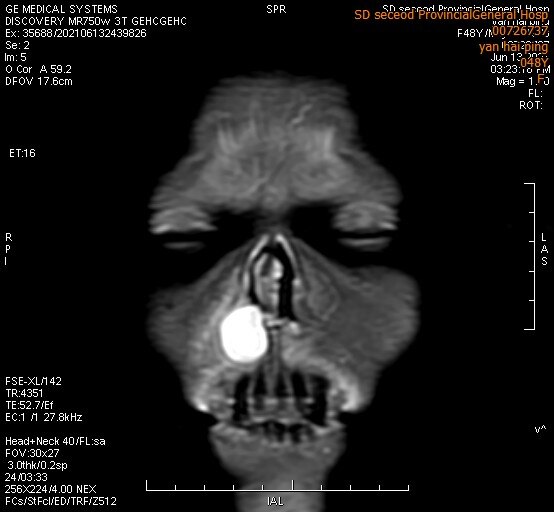

鼻前庭癌是指来源于鼻前庭的恶性肿瘤,表现为鼻腔内的溃疡或肿块,可伴有鼻出血。鼻前庭癌的病理学检查大部分都是鳞状细胞癌。 鼻前庭癌极其少见,患者大都是 60 岁以上的老年人,男性多于女性。吸烟的人更容易患鼻前庭癌。鼻前庭炎一般治疗 1、西医治疗 消炎消肿,洁净痂皮,去除病因,改正挖鼻习惯。 局部用鼻软膏、抗生素软膏,每日34次,若有皲裂可先用10%硝酸银液烧灼。 对急性病例可局部加用热敷或红外线理疗,重症可全身加用抗炎药物。鼻前庭炎(vestibulitis of nose)系鼻前庭 皮肤的弥漫性炎症,多为两侧。 经常挖鼻,急、慢性鼻炎和鼻窦炎、变态反应或鼻腔异物(多见于小儿)的分泌物刺激,长期在粉尘(如水泥、石棉、皮毛、烟草等)环境中工作,易诱发或加重本病。

鼻前庭囊肿是什么 影像检查有哪些

鼻前庭囊肿鼻内镜下电动切割揭盖术与唇龈沟径路切除术的临床分析

Cl2936 典型的双侧鼻前庭囊肿 不能再典型了 典型病例医影在线